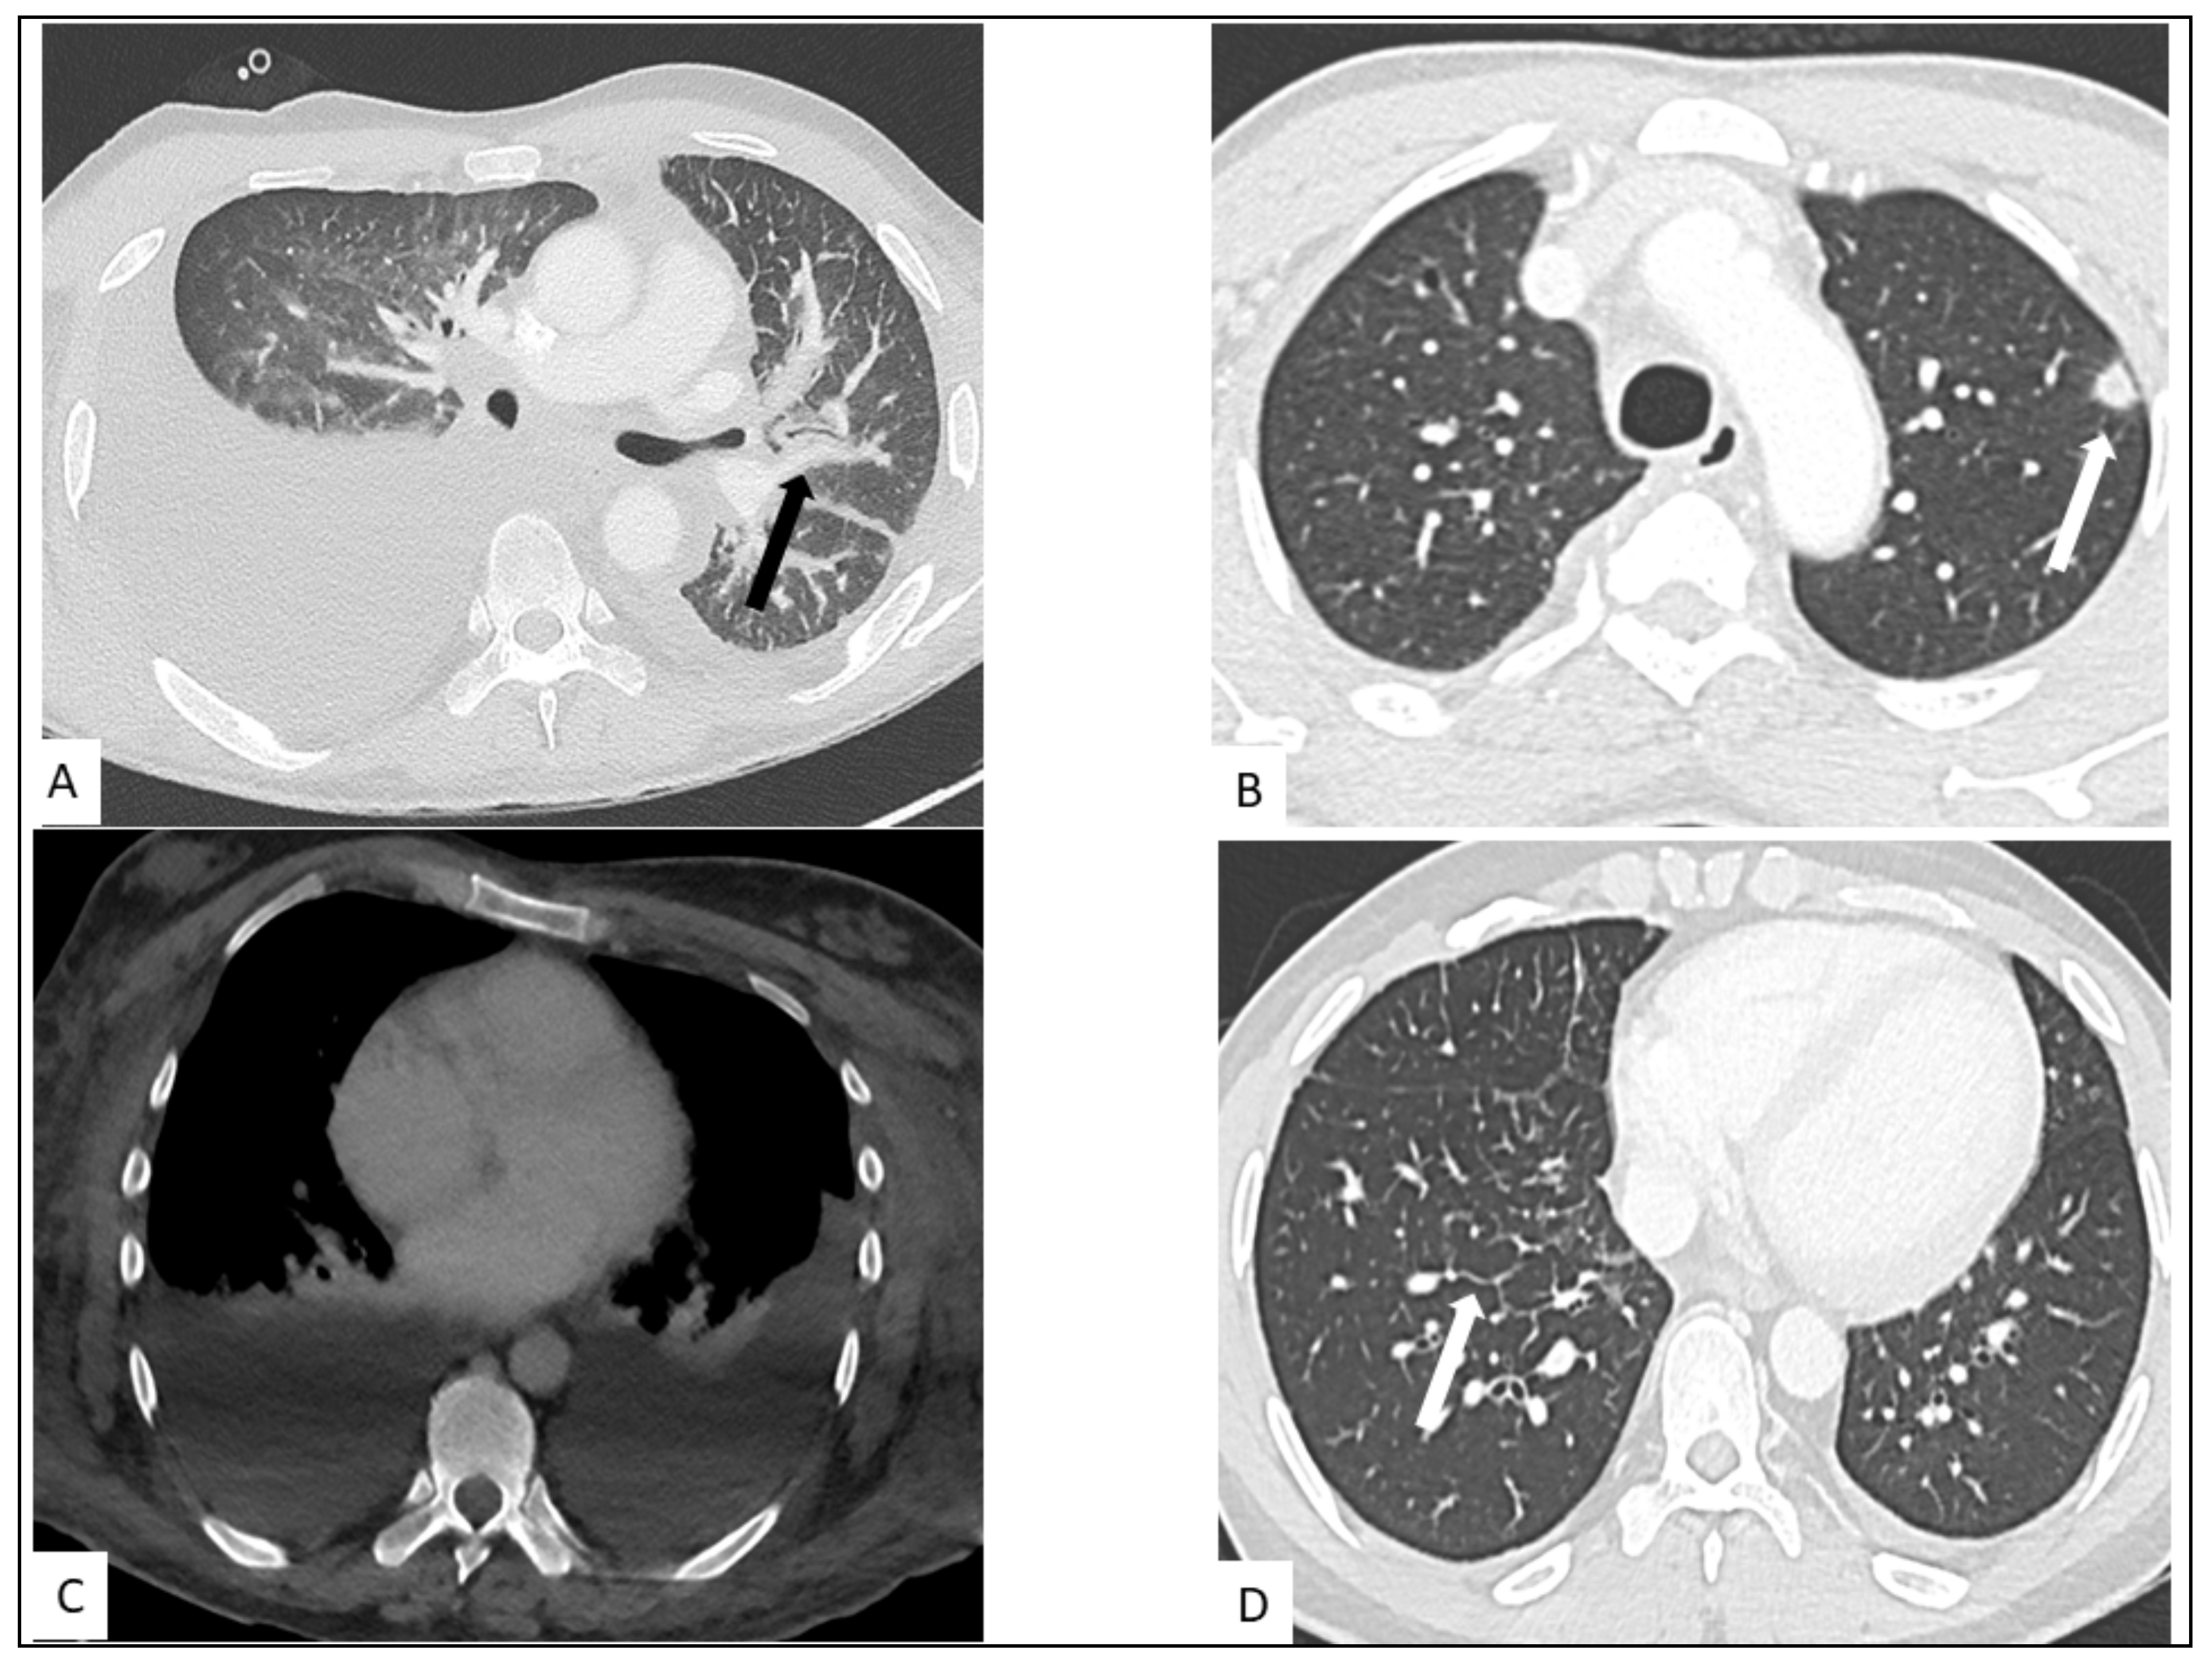

5.1. Pulmonary KS

5.2. Hepato-Splenic KS

5.3. Other Visceral Involvement